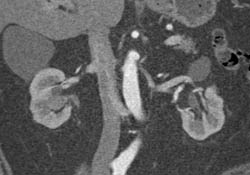

Transitional Cell Cancer (TCC) of Right Kidney